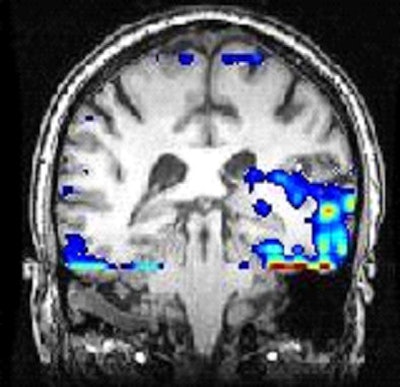

| MEG coherence mapping image overlaid on MRI scan in patient with unilateral tinnitus shows left auditory cortex is significantly more active. |

In the study, the researchers analyzed magnetoencephalography scans from 17 patients with tinnitus and 10 patients without tinnitus. In tinnitus patients who have ringing in one ear, MEG detected the greatest amount of activity in the auditory cortex on the opposite site of the brain from their perceived tinnitus.

For patients with ringing in the head or both ears, MEG revealed activity in both hemispheres of the brain, with greater activity appearing in the opposite side of the brain of the strongest perception of tinnitus.